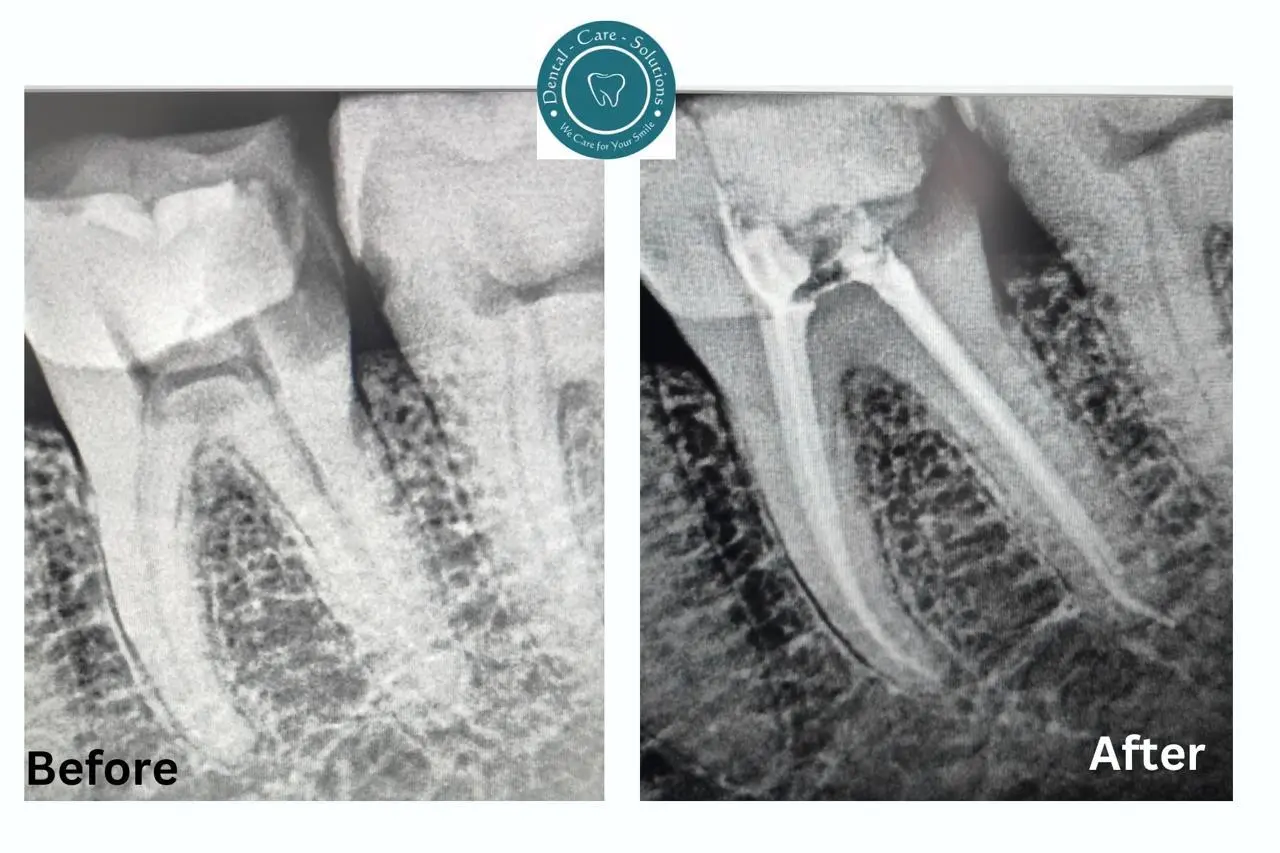

Root Canal Gallery

Root canal treatment involves removing the infected or damaged pulp from inside the tooth to prevent further infection, preserve the tooth, and alleviate pain.

Filling & Sealing